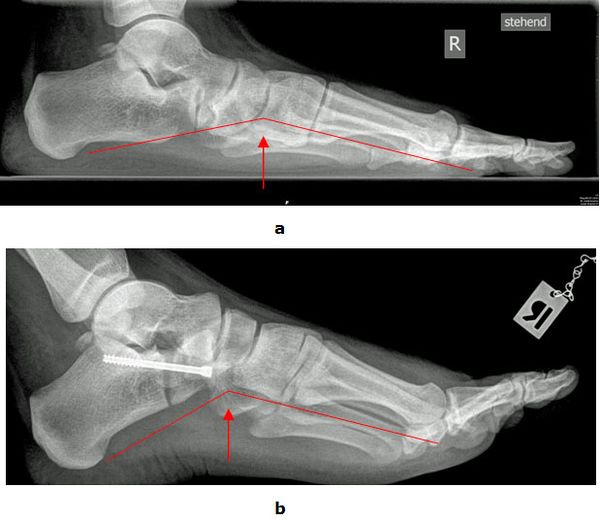

Achsanalyse durch Röntgen Belastungsaufnahmen

In der Röntgendiagnostik werden Belastungsaufnahmen des Fußes zur Bestimmung der Achsverhältnisse durchgeführt. Entscheidend ist das Verhältnis zwischen dem ersten Mittelfußknochen und dem Sprungbein sowie der Öffnungswinkel zwischen Fersenbein und Sprungbein. Die Winkel sind beim Plattfuß vergrößert. Außerdem wird der Gelenkzustand beurteilt.

Abb.3: a Absenkung des Längsgewölbes im Röntgenbild. Krankhafte Veränderung der Knochenachsen.

b Durch eine gelenkerhaltende Operationsmethode (Verlängerung des Fersenbeins (Evans Osteotomie, Calcaneus Verlängerungs Osteotomie) konnte der Fuß wieder aufgerichtet werden.